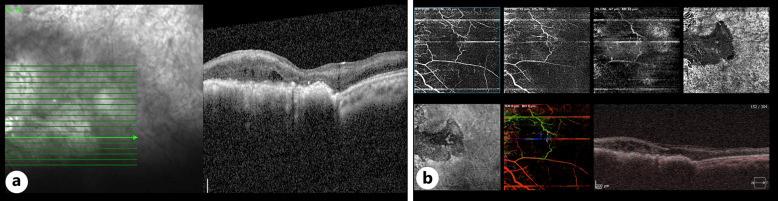

We describe a case of unilateral retinal ischemia in the setting of combined central retinal artery and vein occlusion with associated proliferation of retinal pigment epithelium. The patient was worked-up for the etiology of her presentation which was found to be antiphospholipid syndrome.

Although pigment epithelial proliferation occurs commonly after retinal ischemia, no study has reported complete multimodal imaging of such a pathology or proposed the possible mechanisms explaining such an association.

我们描述了一例在视网膜中央动脉和静脉联合阻塞及视网膜色素上皮细胞增生情况下发生的单侧视网膜缺血病例。对该患者进行了病因检查,发现病因是抗磷脂综合征。

尽管色素上皮细胞增生在视网膜缺血后很常见,但尚无研究报道过此类病变的完整多模态成像,也未提出解释这种关联的可能机制。